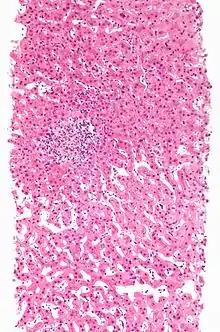

A rash due to a drug reaction |